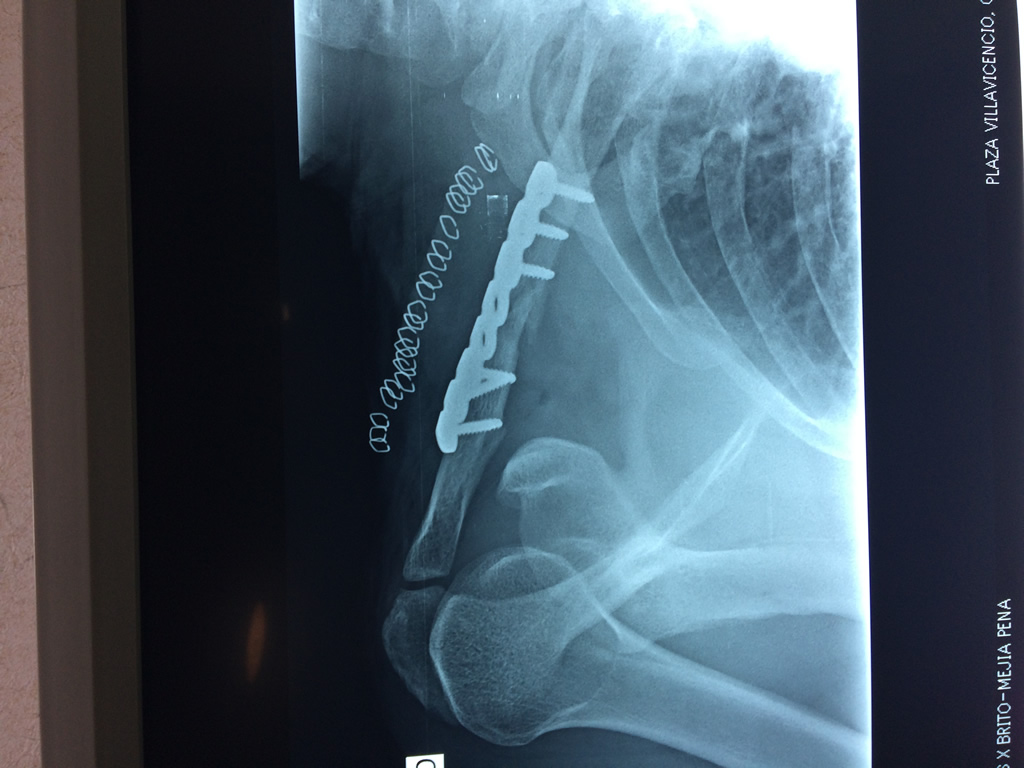

Fémur - Clavícula

La clavícula es un hueso largo, con forma de "S" itálica, situado en la parte anterosuperior del tórax. Junto con la escápula forman la cintura escapular. Se puede palpar por toda su longitud y se extiende del esternón al acromion de la escápula, siguiendo una dirección oblicua lateral y posterior.

Se considera el único medio de unión entre el miembro superior y el tórax. A pesar de su aspecto, similar al de un hueso largo, posee una estructura semejante a la de un hueso plano, ya que carece de epífisis y de diáfisis, lo que la harían entrar dentro de la clasificación de hueso largo. Carece de un canal medular propiamente dicho.